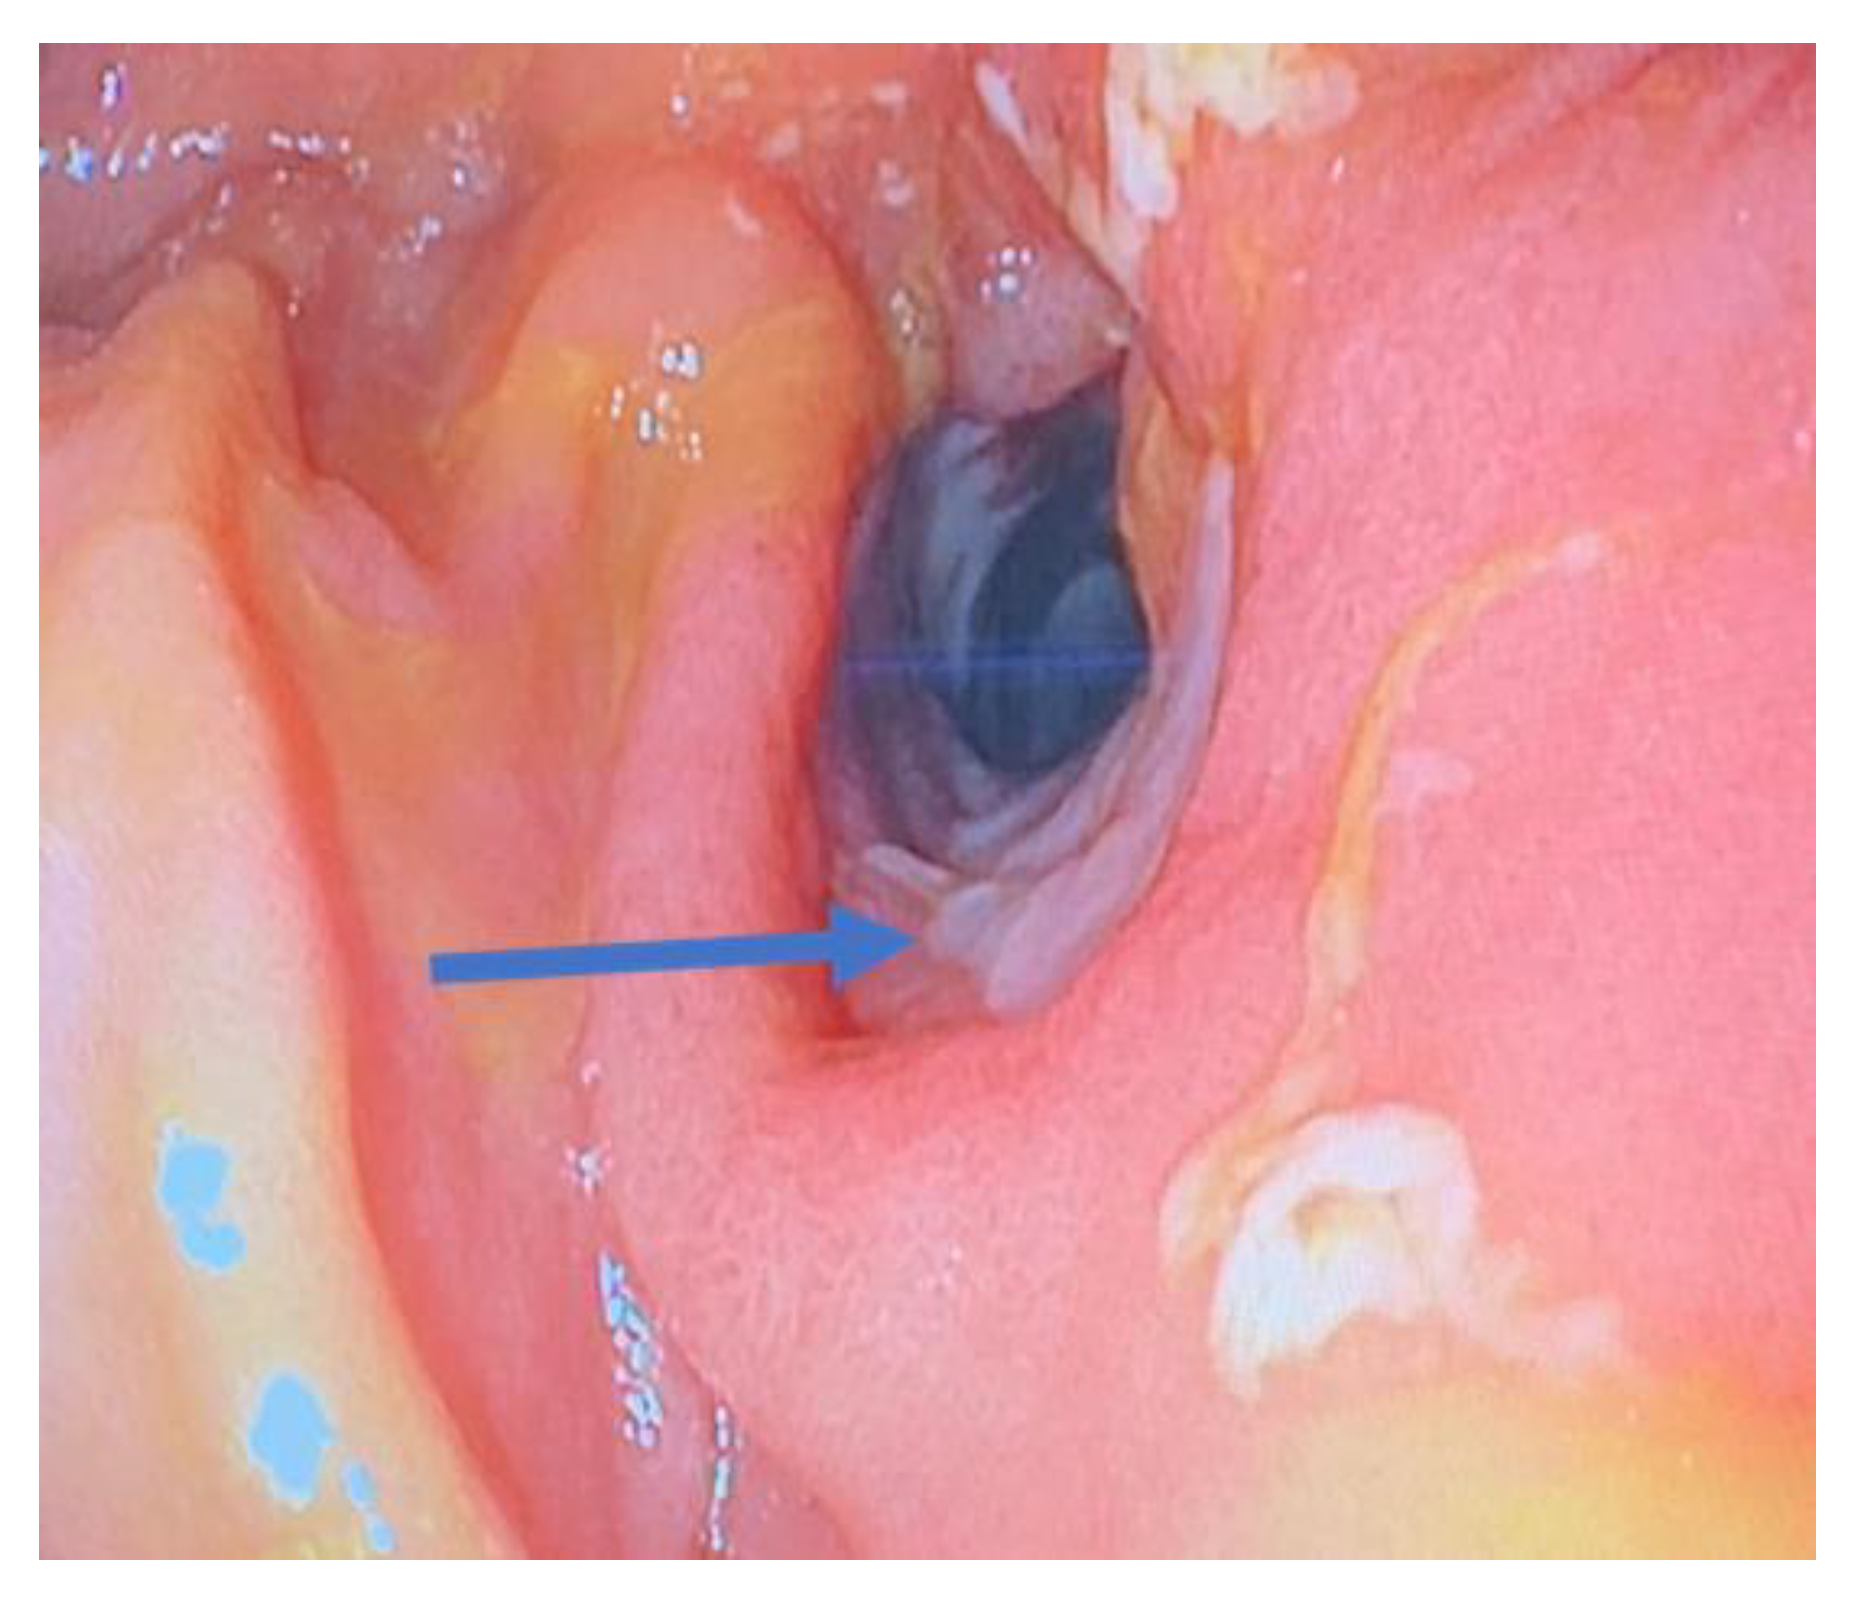

- Endoscopic dilation